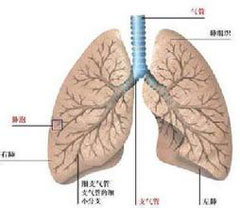

肺栓塞和下肢静脉血栓

疾病介绍:肺栓塞、肺动脉高压肺栓塞(pulmonary embolism, PE)是以各种栓子阻塞肺动脉系统为其发病原因的一组疾病或临床综合征的总称,以下肢静脉血栓脱落引起…【详细】

肺栓塞和下肢静脉血栓

疾病介绍:肺栓塞、肺动脉高压肺栓塞(pulmonary embolism, PE)是以各种栓子阻塞肺动脉系统为其发病原因的一组疾病或临床综合征的总称,以下肢静脉血栓脱落引起…【详细】

肺栓塞和下肢静脉血栓

疾病介绍:肺栓塞、肺动脉高压肺栓塞(pulmonary embolism, PE)是以各种栓子阻塞肺动脉系统为其发病原因的一组疾病或临床综合征的总称,以下肢静脉血栓脱落引起…【详细】

肺栓塞和下肢静脉血栓

疾病介绍:肺栓塞、肺动脉高压肺栓塞(pulmonary embolism, PE)是以各种栓子阻塞肺动脉系统为其发病原因的一组疾病或临床综合征的总称,以下肢静脉血栓脱落引起…【详细】

肺栓塞和下肢静脉血栓

疾病介绍:肺栓塞、肺动脉高压肺栓塞(pulmonary embolism, PE)是以各种栓子阻塞肺动脉系统为其发病原因的一组疾病或临床综合征的总称,以下肢静脉血栓脱落引起…【详细】

肺栓塞和下肢静脉血栓

疾病介绍:肺栓塞、肺动脉高压肺栓塞(pulmonary embolism, PE)是以各种栓子阻塞肺动脉系统为其发病原因的一组疾病或临床综合征的总称,以下肢静脉血栓脱落引起…【详细】

肺栓塞和下肢静脉血栓

疾病介绍:肺栓塞、肺动脉高压肺栓塞(pulmonary embolism, PE)是以各种栓子阻塞肺动脉系统为其发病原因的一组疾病或临床综合征的总称,以下肢静脉血栓脱落引起…【详细】